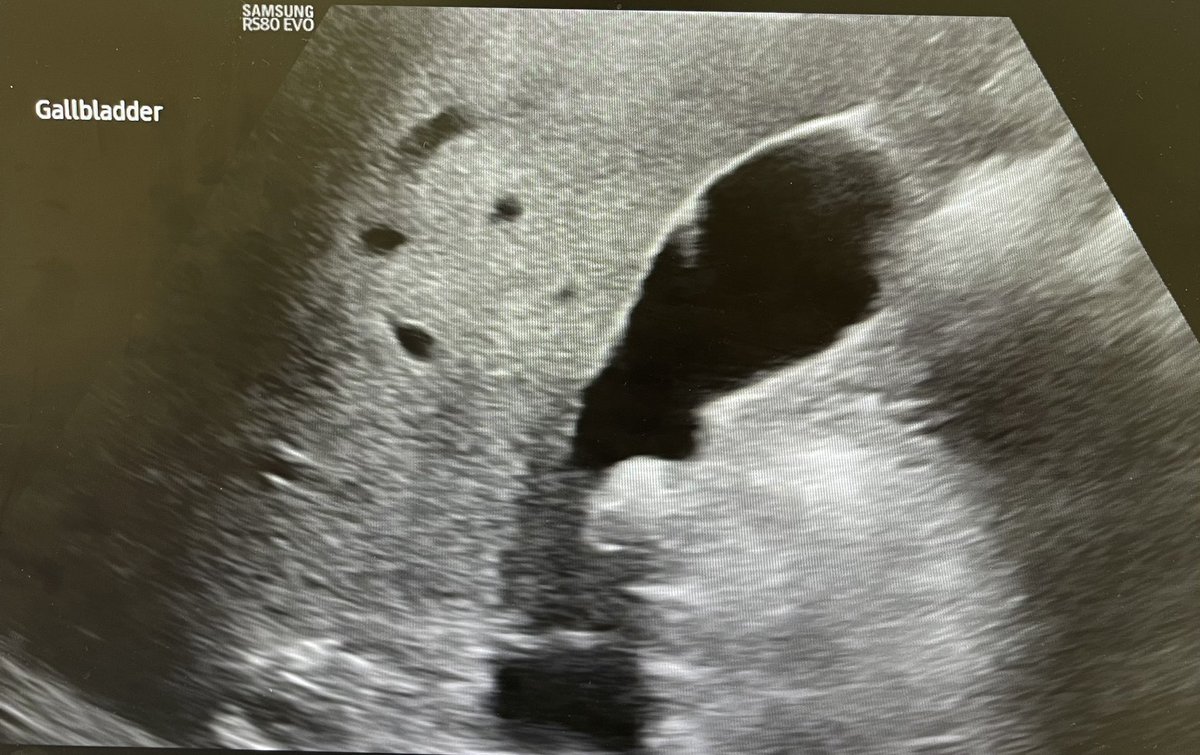

Gallbladder polyp, dilated CBD, diffuse heterogenous spleen appearance. Any differentials on the spleen? @Rad_Munagi @Chinons14125586 @ChroRadGirlie @EdokiTheophilu2 @AjuboDaso @UnegbuVivi27491